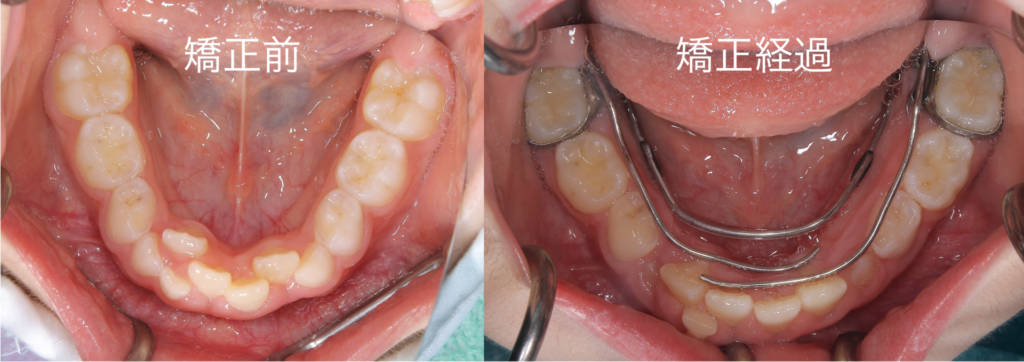

写真のように、特に下顎の前歯にガタつきが生じていました

現状の評価と致しましては、下顎のアーチが狭く歯が並ぶスペースが少ないため、前歯がガタついていると判断いたしました

治療の経過ですが、アーチが広がり歯が整列してきていることが認められます